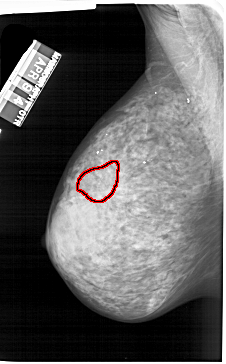

A_1242_1.LEFT_MLO

FILE: A_1242_1.LEFT_MLO.OVERLAY

TOTAL_ABNORMALITIES 1

ABNORMALITY 1

LESION_TYPE CALCIFICATION TYPE PUNCTATE DISTRIBUTION CLUSTERED

ASSESSMENT 4

SUBTLETY 2

PATHOLOGY BENIGN

TOTAL_OUTLINES 1

BOUNDARY